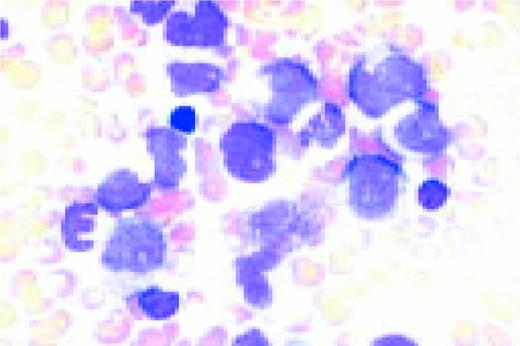

Slide L28

Reactive plasmacytosis with circulating plasma cells. Composite: blood (L) and bone marrow (R). This 71-year-old male was admitted because of fever (38.3°C) and suspected cholangitis. The WBC was 15.4 × 109/L with 10% plasma cells. A bone marrow aspirate showed about 30% small plasma cells with deep blue cytoplasm. A diagnosis of multiple myeloma with circulating plasma cells was considered. The total protein was not increased. The gamma globulin fraction was 40%. Agar electrophoresis revealed several monoclonal components. In the immunoelectrophoresis, the major component appeared to be a IgM-kappa paraprotein. The normal immunoglobulins were not decreased. Immunophenotyping of the blood plasma cells proved the polyclonality of these cells with a kappa/lambda ratio of 55/45. After treatment of the infection, plasma cells disappeared from the blood.FIG28